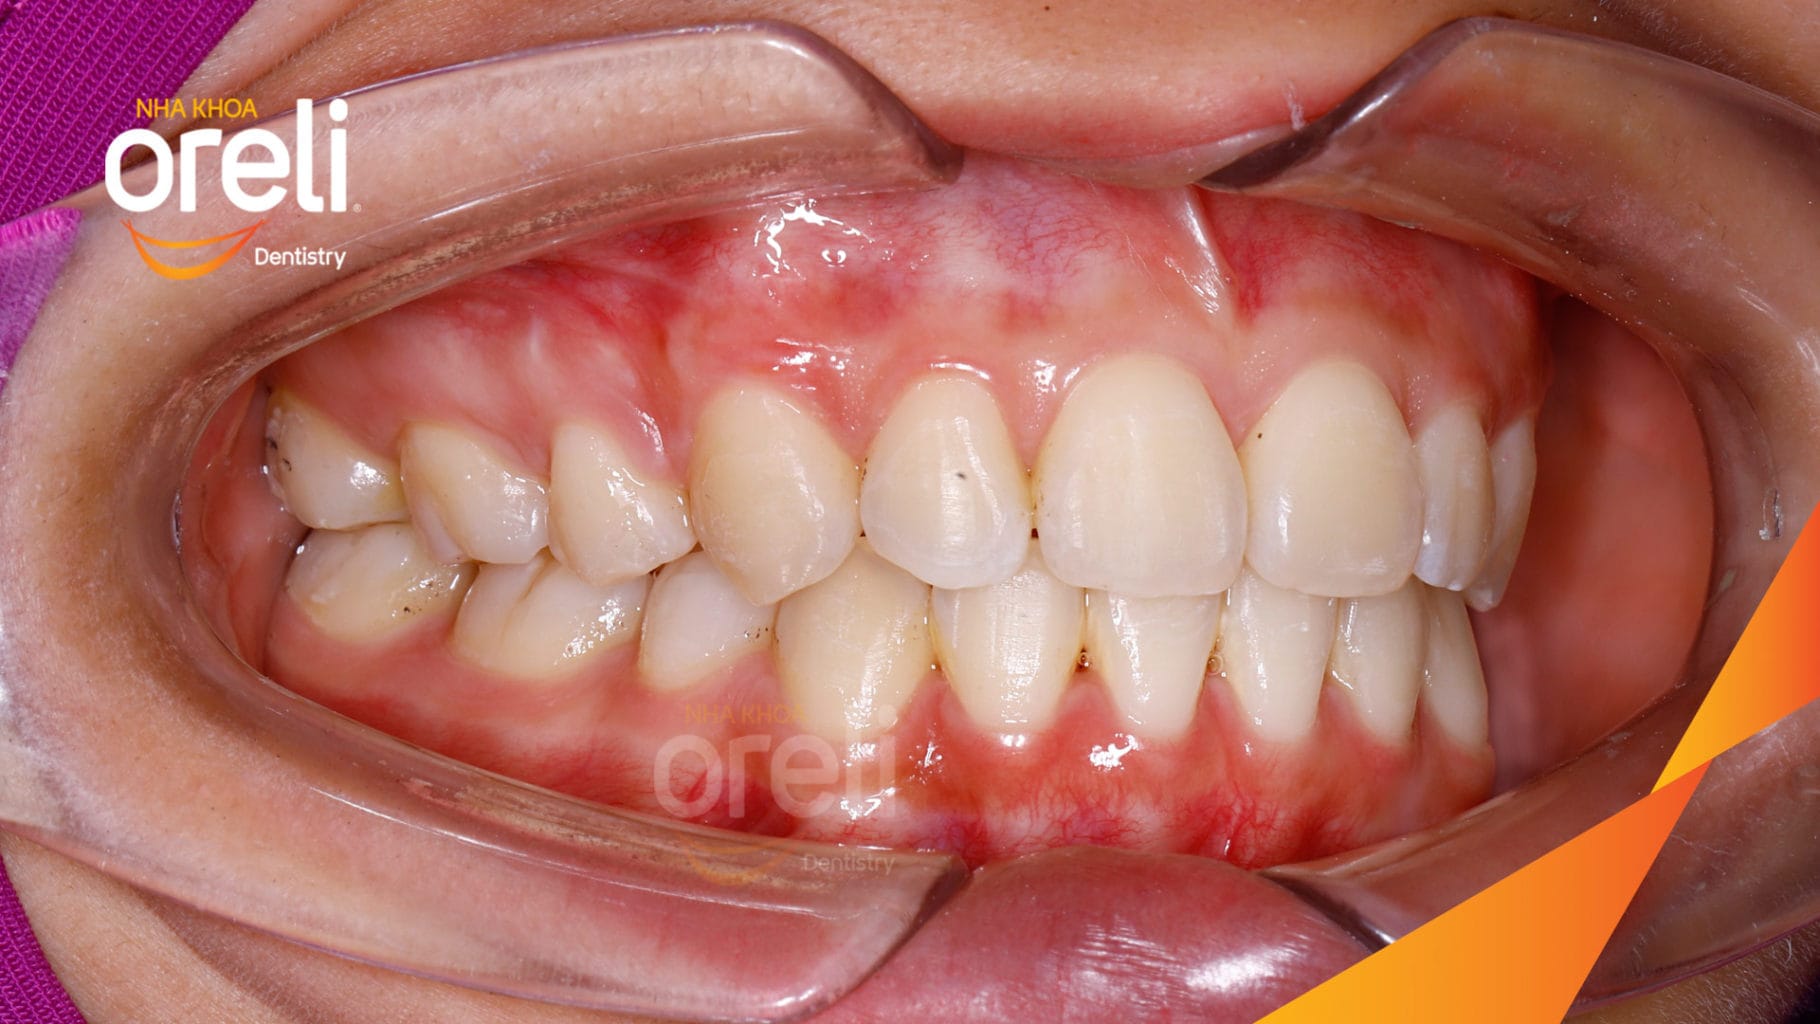

Kết quả: Khớp cắn đúng nụ cười tự nhiên, góc mặt nghiêng đẹp

Xin chào bạn. Trong trường hợp răng hô có độ nhô môi quá mức cho phép, để cải thiện mặt nghiêng và trục răng cửa thì niềng răng hô có nhổ răng 4 là một trong những giải pháp cần thực hiện.

Trong trường hợp này độ nhô môi lớn, góc mũi môi nhọn, môi trên và dưới trượt ra trước so với đường thẩm mỹ E của Rickket, trục răng cửa hàm trên ngả trước nhiều. Việc nhổ răng 4 để giảm hô được thực hiện.